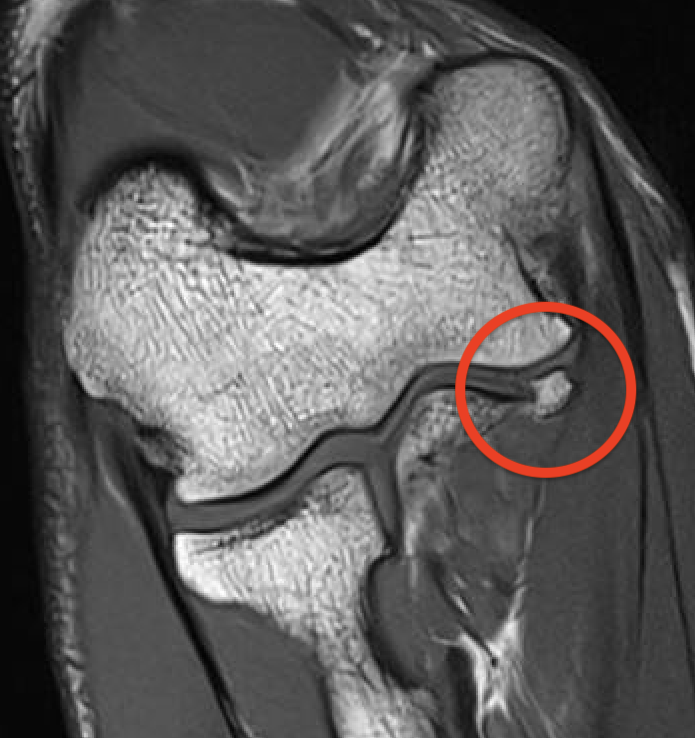

MRI

Intact

Grading of tears

Proximal / midsubstance / distal injury

Partial tears - low grade versus high grade

Complete tears

Acute full thickness UCL tear

High grade partial distal UCL tear

Bony avulsion UCL complex medial epicondyle

Bony avulsion UCL sublime tubercle